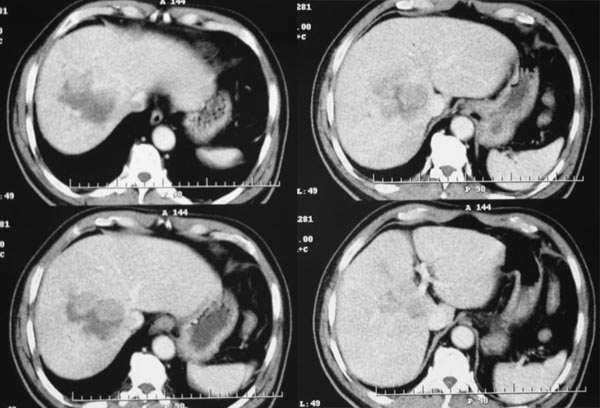

患者,m,71y,乏力、纳差、巩膜黄染两月余,b超示肝内占位性病变。

平扫

动脉期

门脉期

延时期

2.病灶特点:平扫呈低密度,密度不均,中央呈更低密度;动脉期病灶周围强化较明显,高于正常肝组织,低于同层主动脉密度,中央坏死区未见明显强化;门静脉期,病灶呈低密度,低于正常肝组织密度。

肿瘤实质的强化特点符合肝癌表现,需要注意的地方还有患者可能存在门脉右支和下腔静脉内癌栓形成,这更加支持肝癌的诊断。

肿瘤的生长特点和强化特点符合纤维板层样肝细胞癌,下腔静脉内在动脉期有充盈缺损,而在静脉期内未见充盈缺损,故不考虑下腔静脉瘤栓形成

强化特点符合肝血管瘤。鉴别:1 hcc:患者年龄较大,且无肝硬化表现,门、腔静脉未见癌栓形成,肝门结构清晰,因此hcc可不予考虑;2  胆管细胞癌:病灶较大,远端未见胆管扩张,肝外未见明显转移征象;3 fnh 强化特点不符合,且其内的星芒状裂隙也不典型。

早期强化不是很明显,血供不是很丰富,与肝实质相比还是呈快进快出的特点,中心裂隙样坏死,支持原发性肝癌。